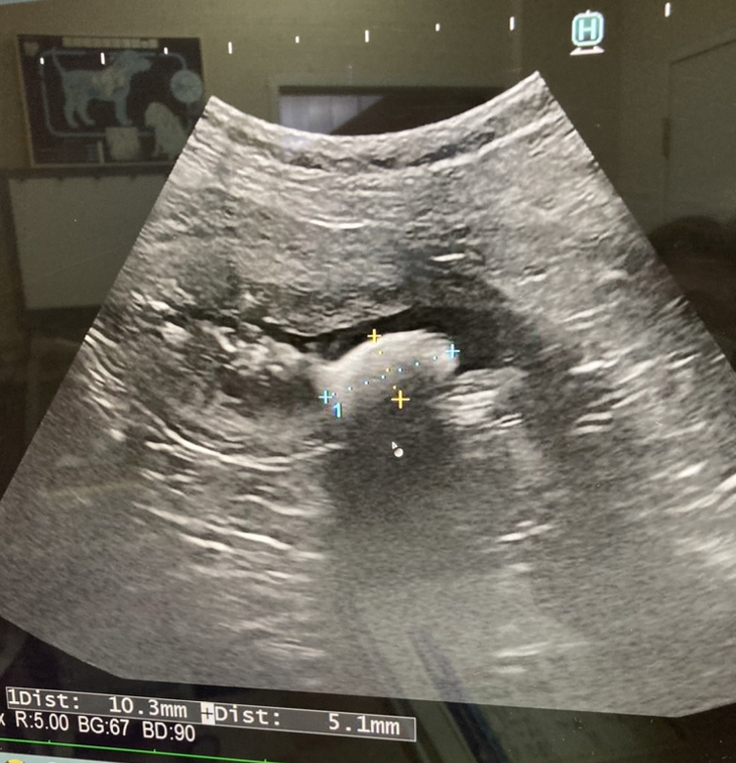

【犬の血尿|シュウ酸カルシウム】

犬の溶けない尿路結石症|で

手術しか完治がない!

膀胱壁の肥厚炎症

がある為

結石が膀胱を痛め

慢性膀胱炎をおこす為

このまま様子を見る猶予はない

との説明を受けました。

下記が診断書になります。

2枚目は拡大してあります。

動物病院からの許可は受けております。

膀胱結石と診断されました。

大きさは1センチを超える物でした。

シュウ酸カルシウムとの事でした。